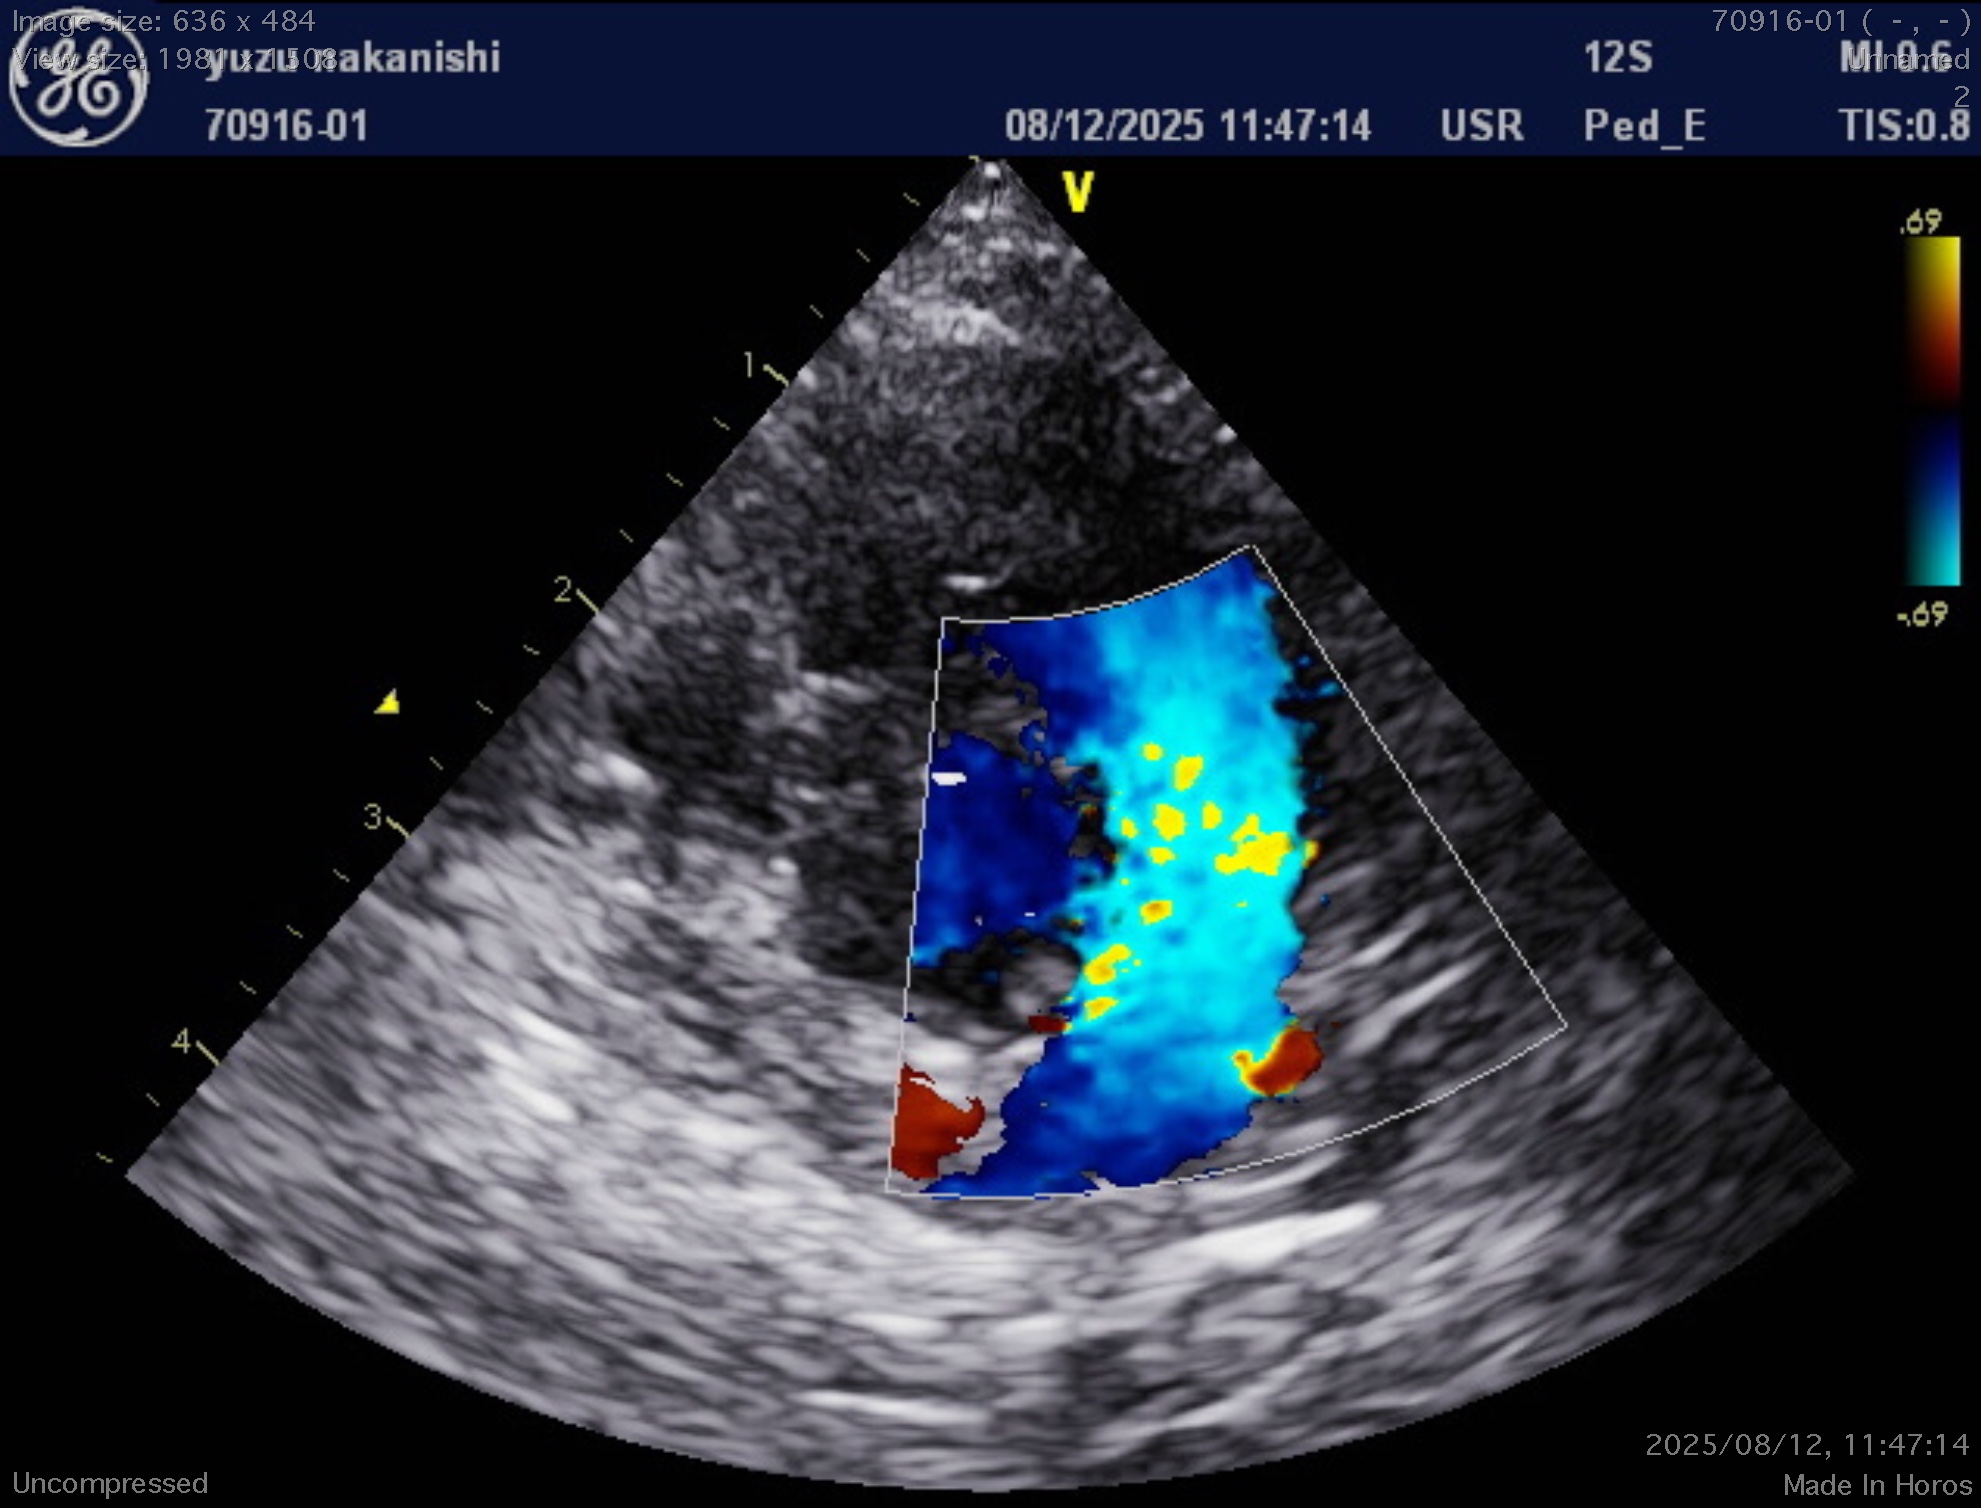

手術の方法や、手術可能かどうかまた現在の治療をどうするかなどことを知るため、超音波(エコー)検査を実施し確定診断します。